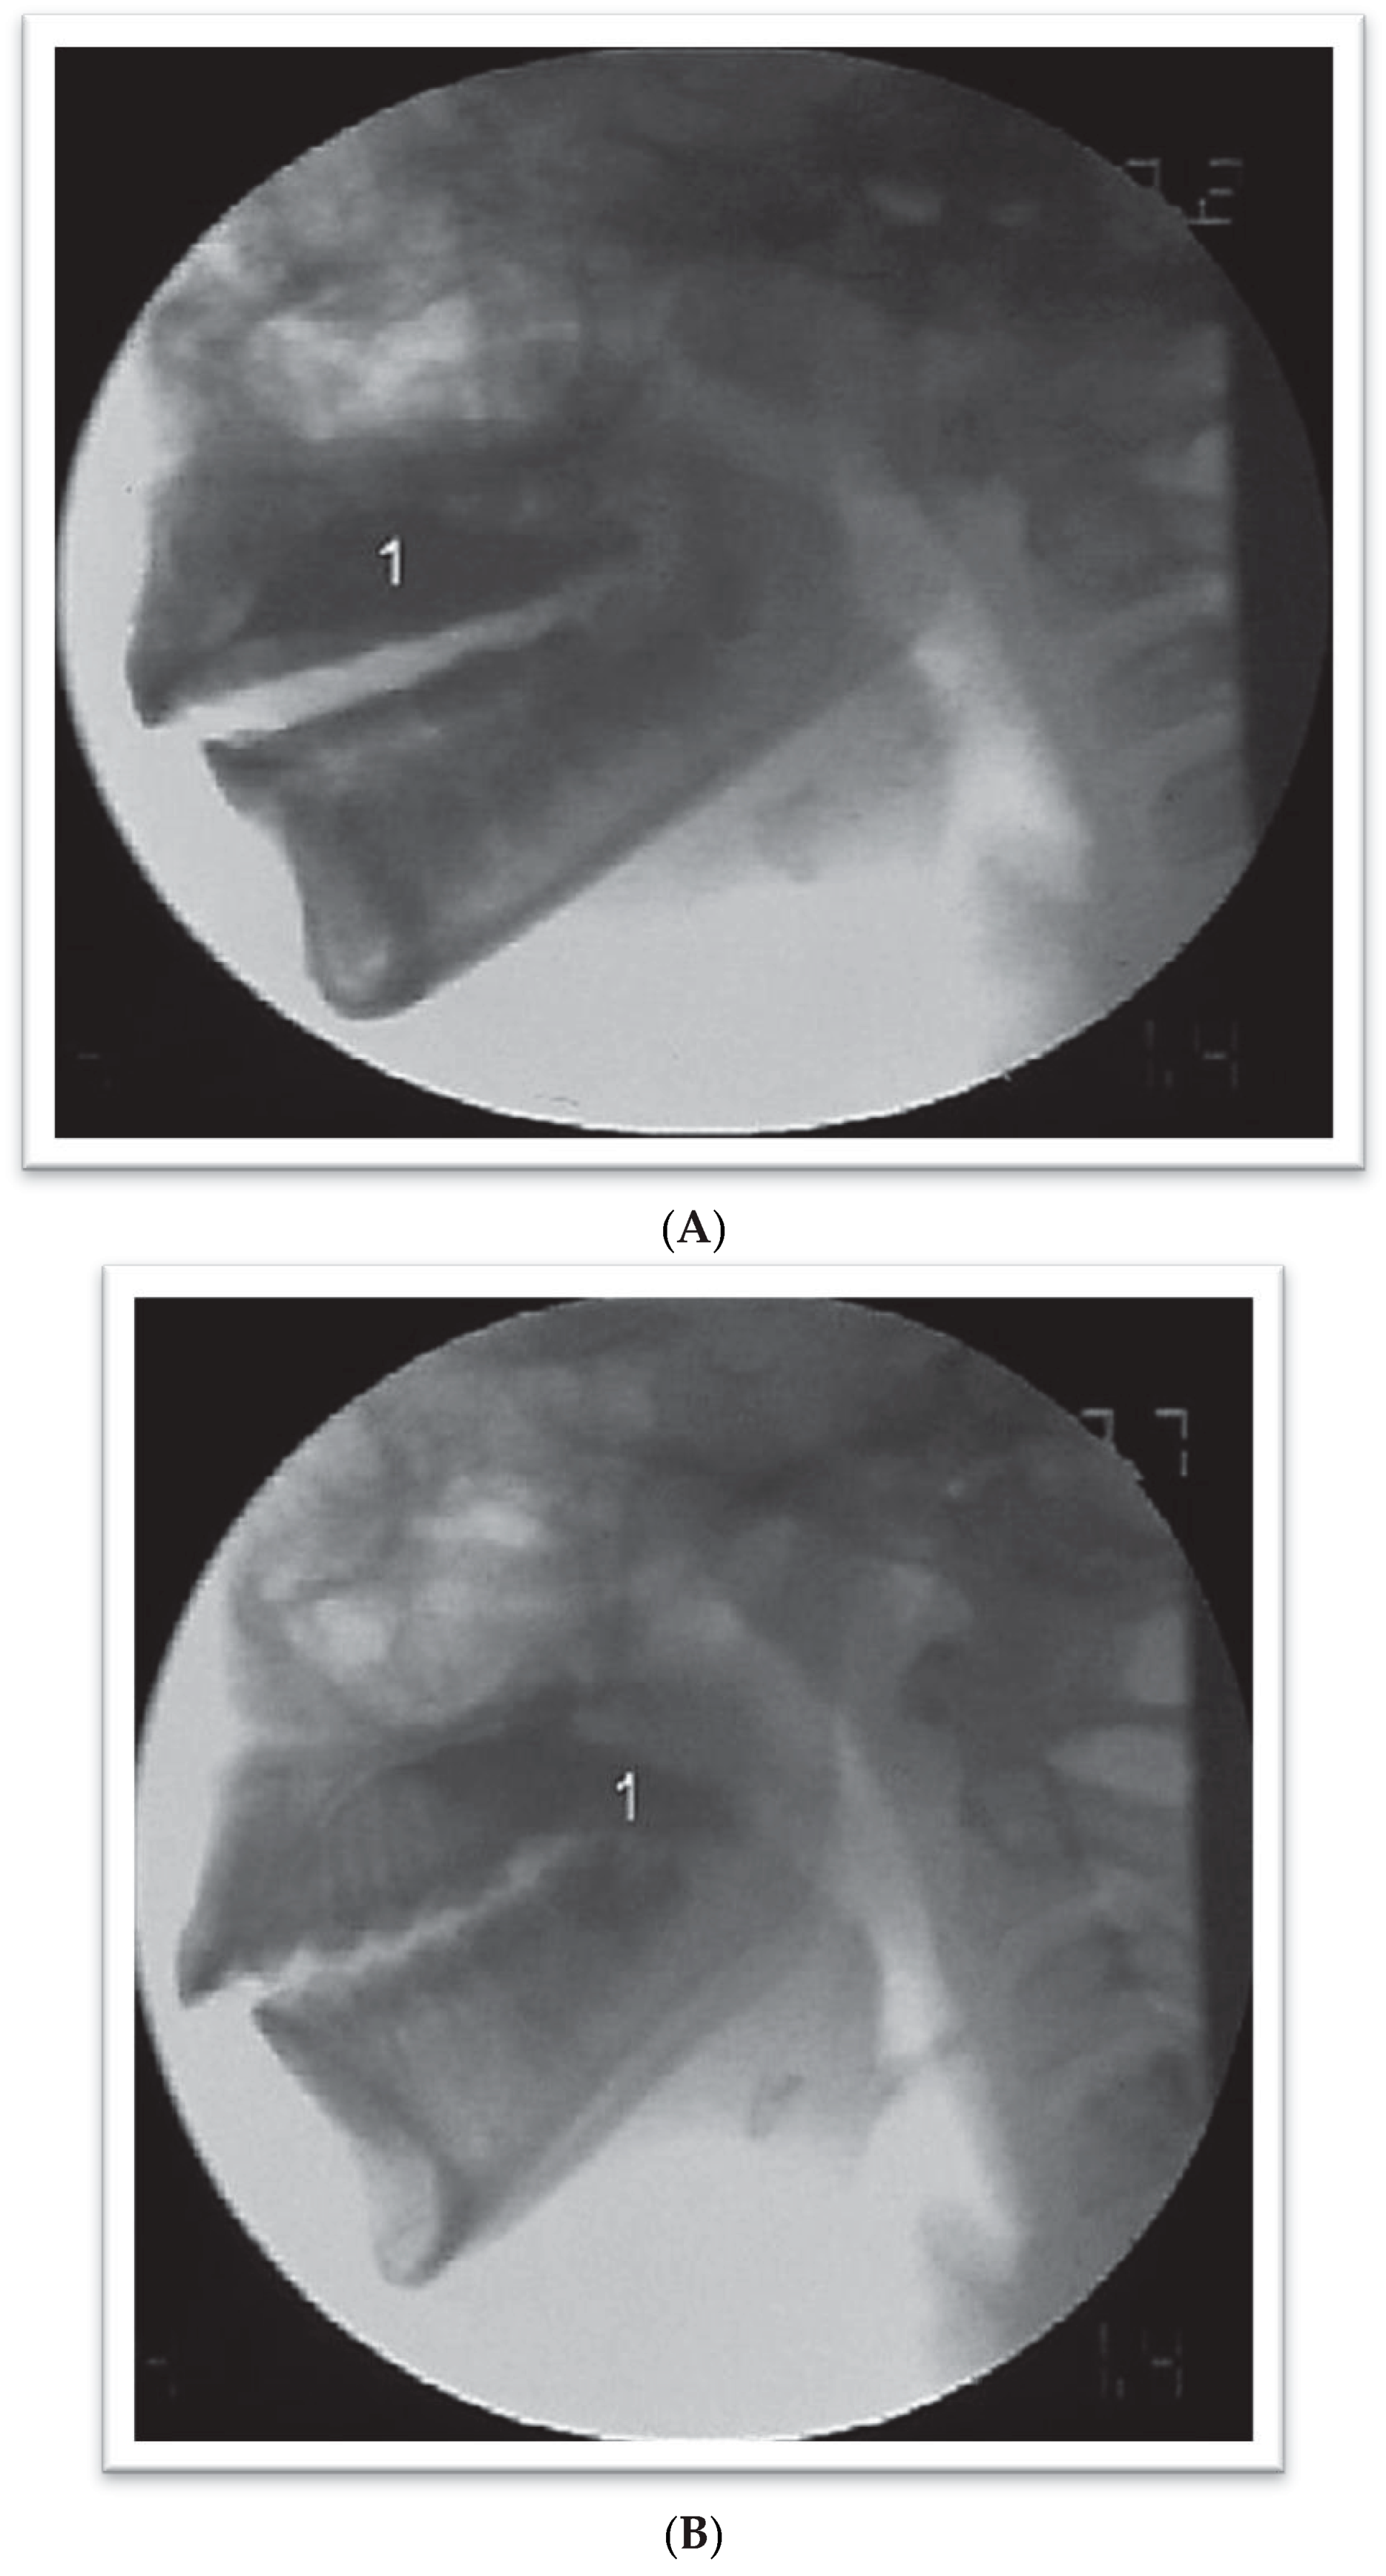

Figure 2. Videofluoroscopic exam on patients with dental malocclusion, Angle Class III type with adaptation defined as Type 1 Adapted Tipper (A and B). (A) Oral Organization Phase. 1—Interposing of the tongue between the upper and the lower dental arch; 2—Contrasted solution organized on the dorsal surface of the tongue. (B) Beginning of the oral ejection phase. 1—Beginning of the projection of the bolus to the pharynx; 2—Escape of part of the contrast from under onto the tongue during ejection; 3—Interposing of the tongue between the upper and the lower dental arch.